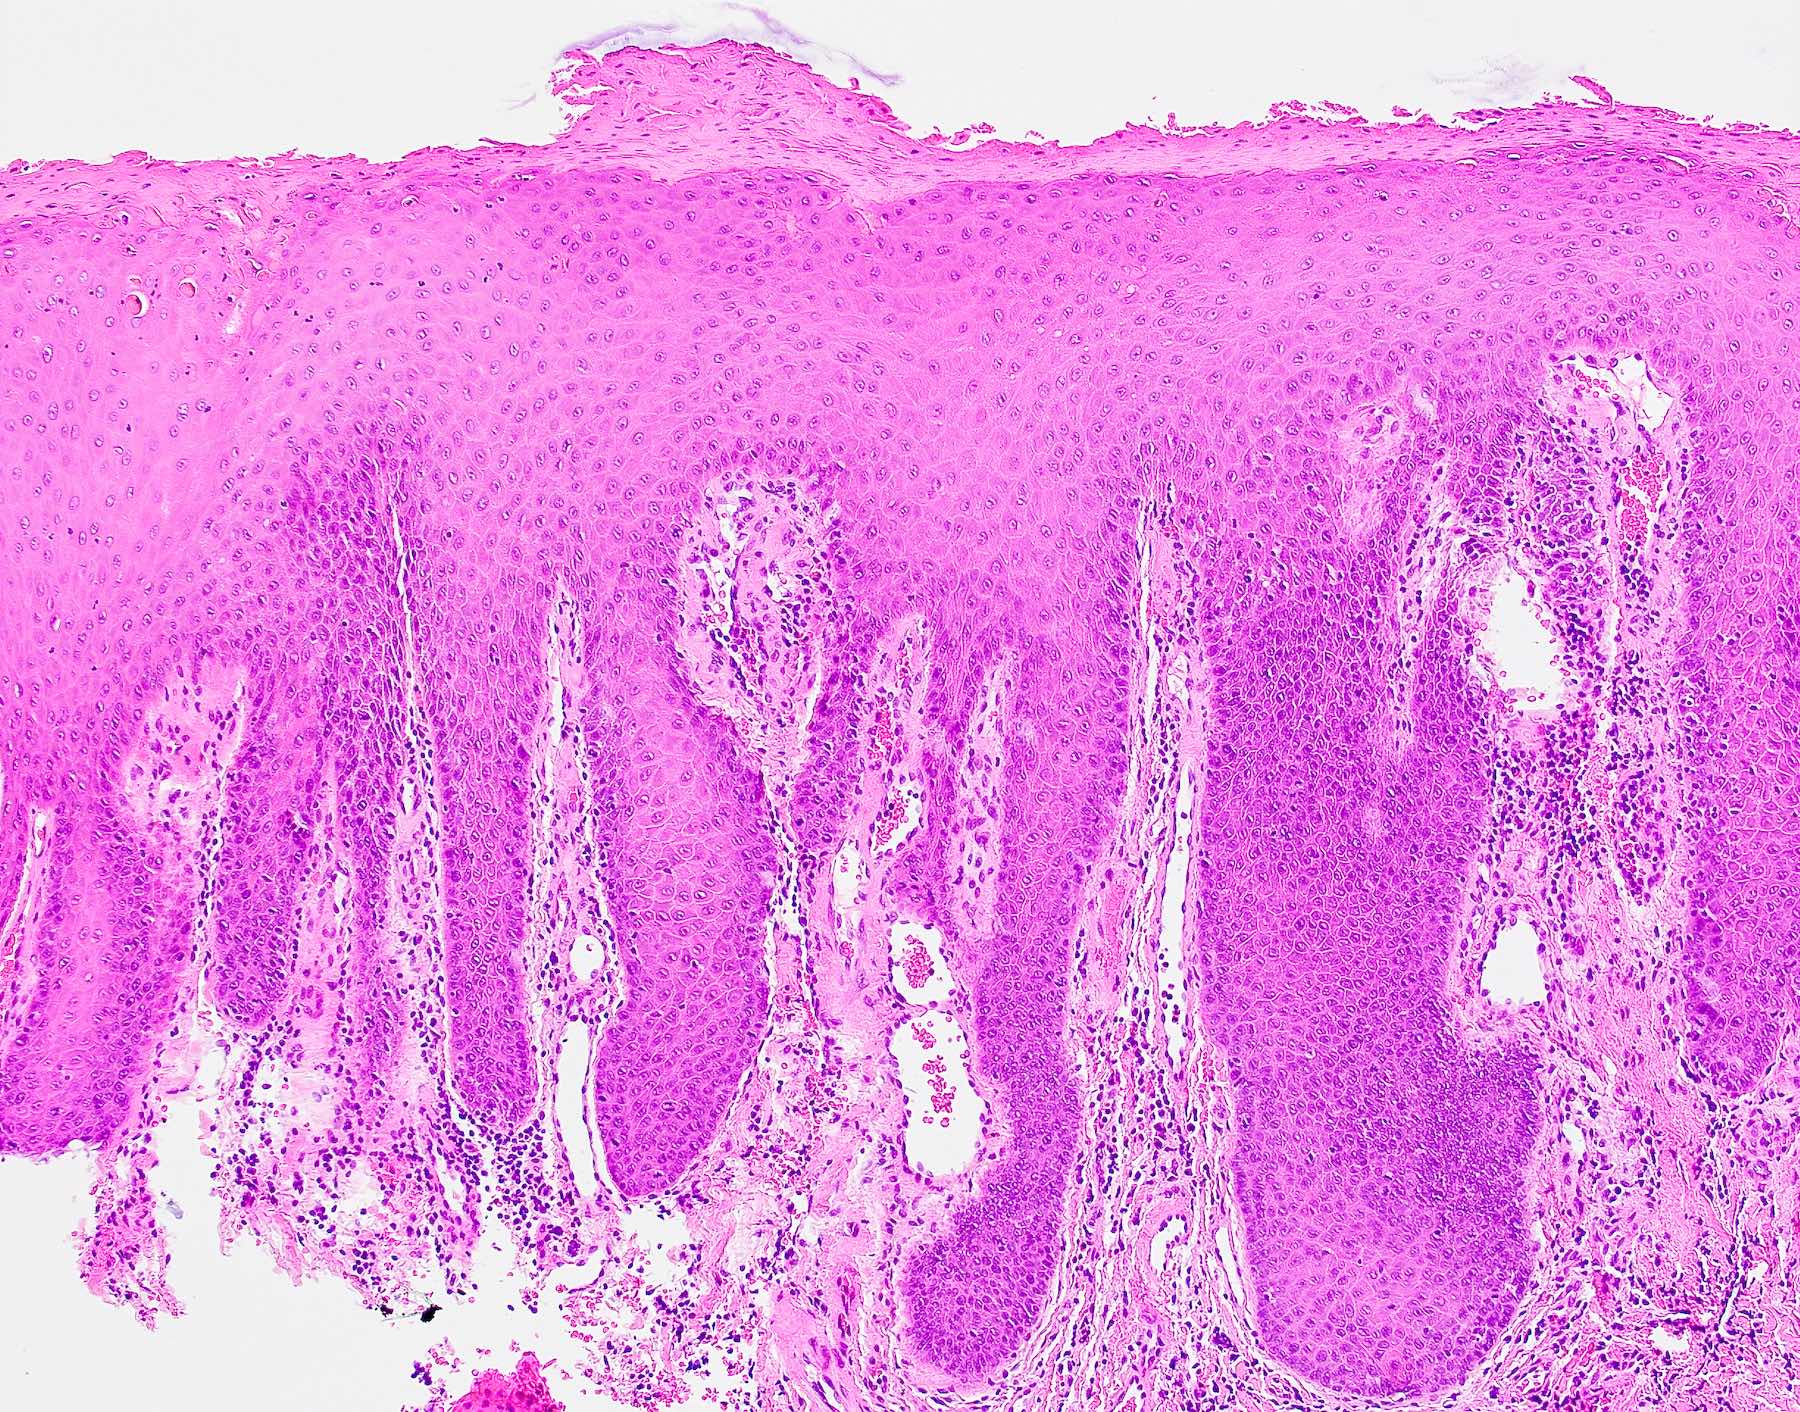

PEH in median rhomboid glossitis

The above biopsy was taken from the posterior dorsal tongue at the midline. What is the microscopic pattern of the epithelium called?

1. Pseudoepitheliomatous hyperplasia

A. Pseudoepitheliomatous hyperplasia. When combined with the clinical information / photograph, the overall diagnosis of this case is median rhomboid glossitis, which is a particular diagnosis made in a patient with a red patch on the middle portion of the posterior dorsal tongue. The epithelium often shows elongated, bulbous shaped rete ridges (pseudoepitheliomatous hyperplasia) and superficial candidal colonization, as highlighted here by a PAS stain. Answer B is incorrect because the epithelium does not show significant atypia or detached islands of invasive epithelium. Answer C is incorrect because there are no salivary ducts pictured above; however, squamous ductal metaplasia may be seen in association with pseudoepitheliomatous hyperplasia in a setting of necrotizing sialometaplasia, a condition most often diagnosed on the hard palate. Answer D is incorrect because although the epithelium is bulbous and hyperplasic, a prominent verrucoid surface architecture and keratin clefting are not identified.